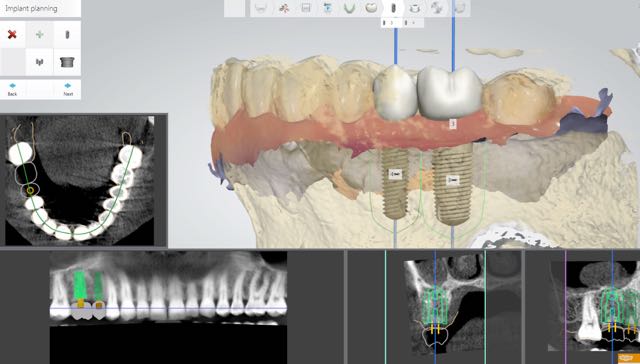

Digital Implant Dentistry- Surgical and Restorative Applications

This master class will provide participants with current digital applications in implant dentistry. We’ll discuss CBCT and optical Scan imaging and how together, they can be used for computer-assisted dental implant dentistry.